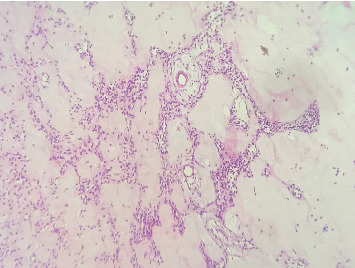

目的:本报告旨在概述罕见的囊性成釉纤维瘤,以促进其与其他牙源性病变(包括牙囊肿和囊性成釉细胞瘤)的区分。病例报告:一名8岁女孩,无明显病史,于1个月前首次发现右侧上颌无痛性肿胀,体积逐渐增大,伴颊皮质单皮质扩张。圆锥束计算机断层扫描显示右侧上颌骨后缘一清晰的单眼低密度病变,大小约为3 × 2 cm;中央骨病变涉及未出牙的第一恒磨牙。保守摘除病变核,同时拔除阻生牙。镜下检查显示良性混合囊性牙源性肿瘤,在粘液样细胞丰富的基质中显示牙源性上皮链和星状成纤维细胞。上皮细胞呈圆形至立方状,无有丝分裂活性或恶性肿瘤征象。整体组织学表现为囊性成釉纤维瘤。结论:囊性成釉纤维瘤的临床和影像学表现与牙源性囊肿相似,因其累及阻生牙。然而,这两种实体在组织学上可以明显区分,因为囊性房颤中所见的富含黏液细胞的基质中独特的牙源性上皮链在含牙囊肿中是不存在的。

Objective: This report is aimed at outlining the unusual cystic variant of ameloblastic fibroma to facilitate its demarcation from other odontogenic lesions, including dentigerous cysts and cystic ameloblastomas. Case Report: An 8-year-old girl with no significant medical history presented to the oral surgery department with a painless swelling in the right maxillary region, first noticed 1 month ago, which gradually increased in size, accompanied by monocortical expansion of the buccal cortex. Cone beam computed tomography revealed a well-demarcated unilocular low-density lesion in the right posterior maxilla, measuring approximately 3 × 2 cm; the central bony lesion involved an unerupted first permanent molar. Conservative enucleation of the lesion was performed, along with the removal of the impacted tooth. Microscopic examination showed a benign mixed cystic odontogenic tumor, displaying odontogenic epithelial strands with stellate-shaped fibroblasts in a myxoid cell-rich stroma. The epithelial cells were rounded to cuboidal, with no mitotic activity or signs of malignancy. The overall histological image suggested a cystic ameloblastic fibroma. Conclusion: Clinically and radiographically, cystic ameloblastic fibroma may resemble a dentigerous cyst due to the involvement of an impacted tooth with the lesion. However, these two entities can be clearly histologically differentiated, as the distinctive odontogenic epithelial strands in a myxoid cell-rich stroma that are seen in cystic AF will be absent in a dentigerous cyst.